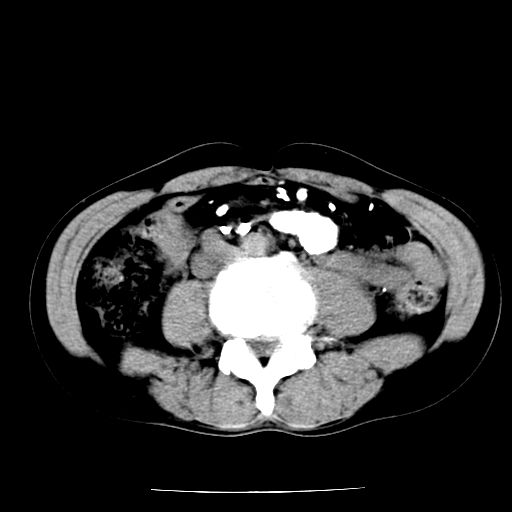

男,59岁,“结核性胸膜炎”30余年,胸部经常疼痛,多次x检查提示“肺部”炎症。腹部疼痛5日,b超提示:“肝内短管结石,余显示不清,建议进一步检查。”

两肺结核并右侧胸腔积液;脾脏、腹腔及腹膜后淋巴结结核[陈旧性];肝内胆管结石

胸部腹部都是结核(双肺。纵隔淋巴结,肝脏,脾脏,肠系膜)

两肺结核并右侧胸腔积液;脾脏、腹腔及腹膜后淋巴结结核[陈旧性];肝内胆管结石。直肠息肉?